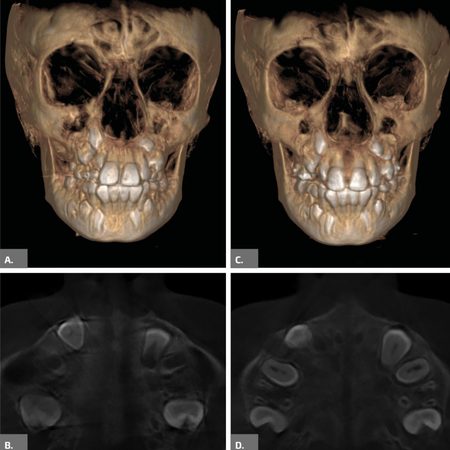

INTRODUÇÃO: O gerenciamento dos espaços das agenesias dentárias é frequentemente relatado como um desafio adicional para o tratamento ortodôntico e, quando associado à má oclusão esquelética, torna o tratamento mais complexo. OBJETIVO: Neste relato de caso, objetivou-se apresentar um tratamento ortopédico seguido de tratamento ortodôntico compensatório de um paciente Classe III esquelética severa com agenesia dentária múltipla. RELATO DE CASO: Paciente do sexo masculino, com 14 anos de idade, teve um plano de tratamento atípico, inicialmente tratado com máscara facial...

INTRODUÇÃO: O gerenciamento dos espaços das agenesias dentárias é frequentemente relatado como um desafio adicional para o tratamento ortodôntico e, quando associado à má oclusão esquelética, torna o tratamento mais complexo. OBJETIVO: Neste relato de caso, objetivou-se apresentar um tratamento ortopédico seguido de tratamento ortodôntico compensatório de um paciente Classe III esquelética severa com agenesia dentária múltipla. RELATO DE CASO: Paciente do sexo masculino, com...

INTRODUCTION: Space management of tooth agenesis is often reported as an additional challenge for orthodontic treatment and, when associated with skeletal malocclusion, makes the treatment more complex. OBJECTIVE: The objective of this case report was to present an orthopedic treatment followed by comprehensive orthodontic treatment of a severe skeletal Class III patient with multiple tooth agenesis. CASE REPORT: A 14-year-old male had an atypical treatment plan, starting with facemask...